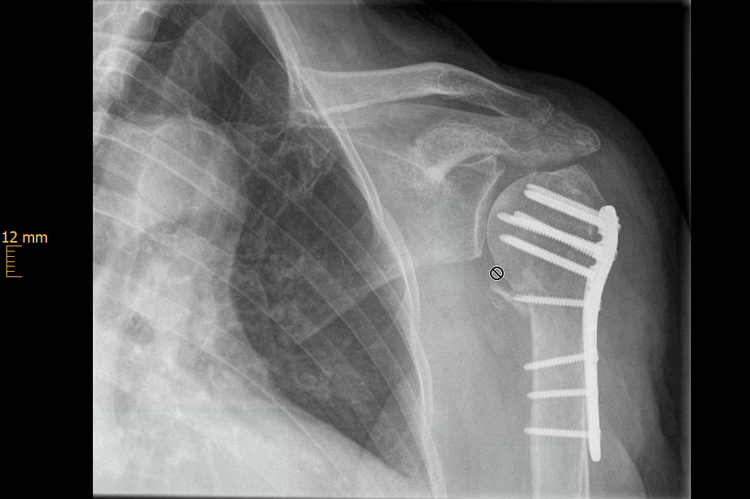

Verschobene Frakturen und solche mit deutlicher Gelenkstufenbildung müssen in der Regel operiert werden. Die Notwendigkeit nimmt dann zu, wenn durch die Fraktur die Oberarmkopfdurchblutung gefährdet ist oder eine starke Verschiebung der Frakturfragmente keine akzeptable Funktion des Schultergelenkes erwarten lässt. Der Vorteil der operativen Behandlung (Osteosynthese) ist neben der möglichst anatomischen Reposition und Stabilisation die frühfunktionelle Nachbehandlung.

In wenigen Fällen besteht auf Grund der Frakturform die Notwendigkeit, das Schultergelenk sofort durch eine Endoprothese zu ersetzen.